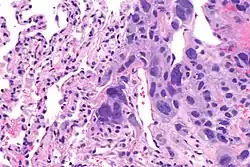

The ovarian yolk sac tumors, also known as endodermal sinus tumors, are accountable for approximately 15.5% of all OGCTs.[8] They have been observed in women particularly in their early ages, and rarely after 40 years of age.[9] The critical pathologic features are a smooth external surface and capsular tears due to their rapid rate of growth. A study consisting of 71 individual cases of ovarian yolk sac tumor provides evidence to the proliferation of the tumor. In one of the cases, the pelvic examination revealed normal activity until a 9 cm and 12 cm sized tumor was discovered 4 weeks later.[9] In another case, a 23 cm tumor was discovered in a pregnant woman who was monitored regularly and had normal findings until oophorectomy became essential.[9] Histologically, these tumors are characterized by mixed solid and cystic components.[1] The mixed solid components are characterized by a soft gray to yellow solid components accompanied with significant hemorrhage and necrosis. The cysts are approximately 2 cm in diameter and populated throughout the tissue which results in giving the neoplasm a ‘honeycombed appearance’.[1]